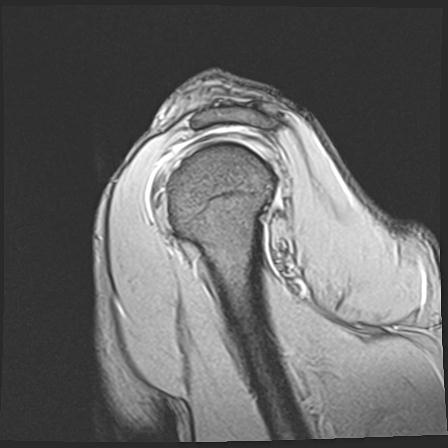

60058 3/9 11/4 右肩 2R+MRI 73歳男性 肩腱板損傷